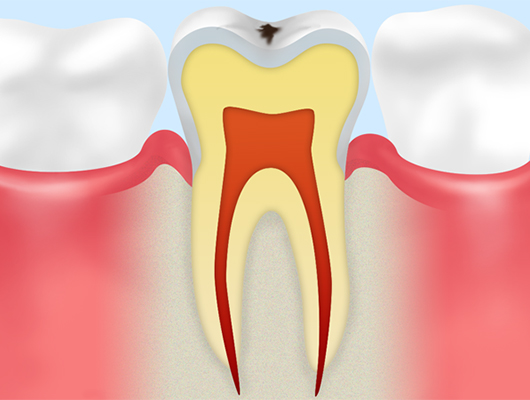

初期のむし歯(CO)歯の表面にあるエナメル質がわずかに溶けている状態です。鏡で見ると歯の表面がザラザラしていたり、白っぽくなっていたりするのが確認できますが、穴はまだあいていません。初期むし歯は適切なブラッシングやフッ素の活用によって、歯を元の健康な状態に戻すことができます。歯を削る必要もありません。 |

エナメル質むし歯(C1)エナメル質の内側にまでむし歯が進行した状態です。先の細い器具で触れると、歯質がやわらかくなっていたり、小さな穴があいていたりするのを確認できます。ただ痛みはなく、人によっては「甘いものがしみる」「冷たいものがしみる」といった症状を感じることがあります。 |